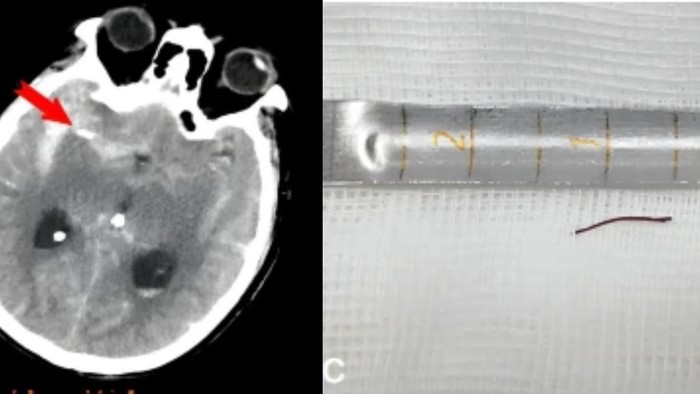

Berdasarkan hasil pemindaian, terlihat ada jarum akupunktur berwarna emas dan agak runcing sepanjang setengah inci atau sekitar 1,27 cm itu bersarang di dalam arteri otak pria tersebut. Hal itu menyebabkan perdarahan internal yang berdampak pada masalah ingatannya.

Jarum kecil di dalam tubuh pria itu ditemukan di arteri yang mengalir melalui otak di belakang mata kanan, yang disebut arteri serebral tengah kanan. Diduga jarum tersebut mungkin patah selama perawatan akupunktur dan kemudian tertancap ke arteri di belakang mata. Penyebab patahnya sampai saat ini masih belum diketahui.

Jarum kemudian dicabut, dan pembuluh darah yang pecah ditutup menggunakan klip logam yang sangat kecil untuk menutup bagian pembuluh yang pecah. Setelah operasi, kondisi pria tersebut awalnya stabil, bahkan alat ventilator yang terpasang di tubuhnya dilepas sepuluh hari kemudian.